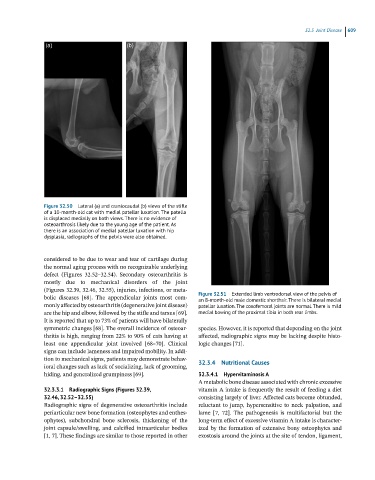

Figure 32.50 Lateral (a) and craniocaudal (b) views of the stifle

of a 10-month-old cat with medial patellar luxation. The patella

is displaced medially on both views. There is no evidence of

osteoarthrosis likely due to the young age of the patient. As

there is an association of medial patellar luxation with hip

dysplasia, radiographs of the pelvis were also obtained.

bolic diseases [68]. The appendicular joints most com- Figure 32.51 Extended limb ventrodorsal view of the pelvis of

an 8-month-old male domestic shorthair. There is bilateral medial

monly affected by osteoarthritis (degenerative joint disease) patellar luxation. The coxofemoral joints are normal. There is mild

are the hip and elbow, followed by the stifle and tarsus [69]. medial bowing of the proximal tibia in both rear limbs.